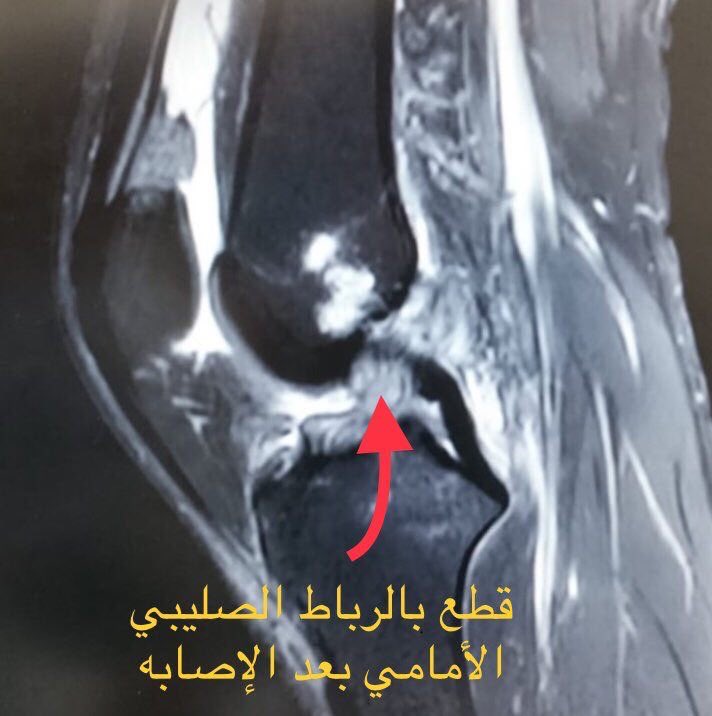

🔺 اسم التخصص : الاشعة التشخيصية

🔺 ماهو تخصص الأشعة ؟

هو علم يهتم بطرق التصوير الطبي بهدف تشخيص وعلاج العديد من الامراض المختلفة ويقوم أخصائي الأشعة بي اجراء الصور المختلفة في قسم الأشعة أو غرف الطوارئ أو العمليات .